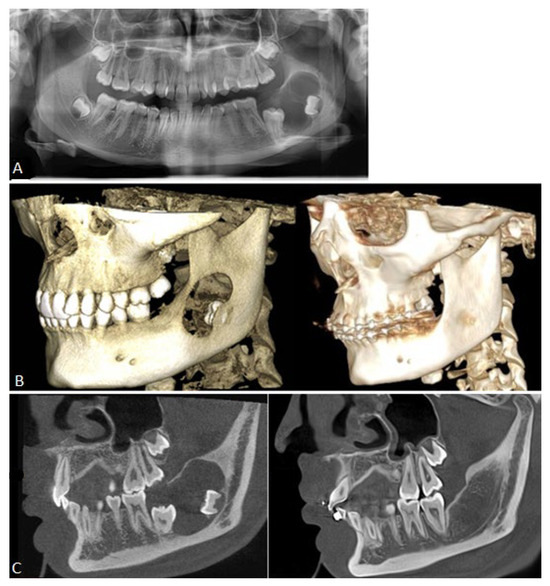

Long-Term Clinical Outcome of a Surgically Treated Ameloblastoma: Over a Decade of Follow-Up and Oral Rehabilitation

Background: Ameloblastomas account for roughly 1% of all jaw tumours and cysts, typically manifesting as slow-growing, painless swellings that expand both buccal and lingual cortical plates and may infiltrate adjacent soft tissue, often leading to a delayed diagnosis. These benign tumours, characterized [...] Read more.

Background: Ameloblastomas account for roughly 1% of all jaw tumours and cysts, typically manifesting as slow-growing, painless swellings that expand both buccal and lingual cortical plates and may infiltrate adjacent soft tissue, often leading to a delayed diagnosis. These benign tumours, characterized by local invasiveness, originate from epithelial tissues and may develop from dental lamina cell rests, the enamel apparatus, the epithelial lining of odontogenic cysts, or basal epithelial cells of the oral mucosa. Methods: This paper aims to describe the comprehensive and interdisciplinary management of an extensive ameloblastoma in a 16-year-old patient, emphasizing the diagnostic challenges, surgical resection, reconstructive procedures, and subsequent oral rehabilitation. Results: At the eleven-year follow-up, clinical and radiographic examinations showed no signs of tumour recurrence. The patient presented no symptoms, indicating neither pain nor functional impairment. The prosthetic rehabilitation utilizing implant-supported fixed restorations was successfully completed, resulting in satisfactory masticatory function and aesthetics. This case adds to the existing evidence on the management of extensive ameloblastomas by demonstrating successful long-term outcomes following interdisciplinary surgical reconstruction and rehabilitation. Conclusions: The presented case highlights the complexity of restoring the lost tissues and functions, as well as the long-term clinical, functional, and aesthetic outcomes over an eleven-years follow-up period. Full article

Figure 1

Oral Rehabilitation Following Surgical Treatment of Mandibular Ameloblastoma: Case Report and Comprehensive Literature Review

Objectives: Ameloblastoma is a locally aggressive odontogenic tumor of the jaws characterized by a high recurrence rate. This work aims to present our clinical experience in managing patient oral rehabilitation following an extensive mandibular ameloblastoma, with a specific focus on mandibular reconstruction [...] Read more.

Objectives: Ameloblastoma is a locally aggressive odontogenic tumor of the jaws characterized by a high recurrence rate. This work aims to present our clinical experience in managing patient oral rehabilitation following an extensive mandibular ameloblastoma, with a specific focus on mandibular reconstruction using a fibula free flap, followed by dental implant placement and prosthetic rehabilitation in a female patient. Additionally, we provide a comprehensive review of the current evidence on surgical management, reconstruction techniques, and long-term outcomes in ameloblastoma treatment. Methods: A 44-year-old female patient presented with a painless swelling in the left mandible. Orthopantomography (OPG) and computed tomography (CT) demonstrated a well-defined radiolucent lesion extending from the canine to the second premolar. An incisional biopsy was performed, and histopathological examination confirmed the diagnosis of mandibular ameloblastoma. The patient underwent segmental resection of the left mandibular body, followed by immediate reconstruction using a vascularized fibular free flap. Eighteen months postoperatively, four dental implants were placed. One implant failed during the osseointegration phase and was removed. Due to residual hard and soft tissue deficiency, prosthetic rehabilitation was achieved with a metal-reinforced resin overdenture, restoring both function and aesthetics. Results: At the three-year follow-up, clinical and radiographic examinations revealed no evidence of tumor recurrence. The patient remained asymptomatic, reporting neither pain nor functional discomfort. Prosthetic rehabilitation with the metal-reinforced resin overdenture was successfully completed, achieving satisfactory masticatory function and aesthetics. Conclusions: The use of the fibula free flap for mandibular reconstruction after ameloblastoma resection provides excellent flexibility, enabling effective bone integration of dental implants. Full article